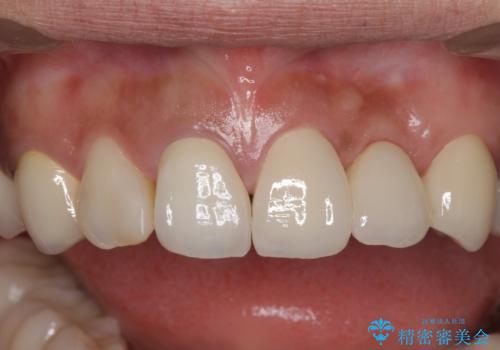

歯を削る量は増えますが、より長い期間再治療なく使用していただくことを最優先に考え、フルカバレッジのオールセラミックブリッジにて補綴することとしました。

外観はもちろんのこと、隙間なく安心して咬むことのできる前歯となり、患者様には大変満足していただきました。